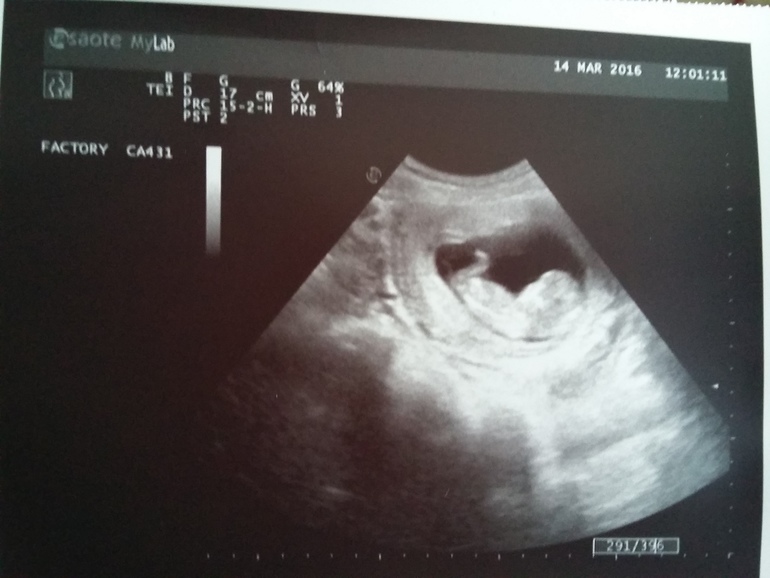

УЗИ НА 13 НЕДЕЛЬКЕ!

Первая фотография нашего малыша!Врач сказал ,что будет мальчишка!Но я все -таки еще надеюсь на принцесску ))Самое главное все хорошо! ЧСС 160.Вес 59 гр,предположили,что будет крупненький.